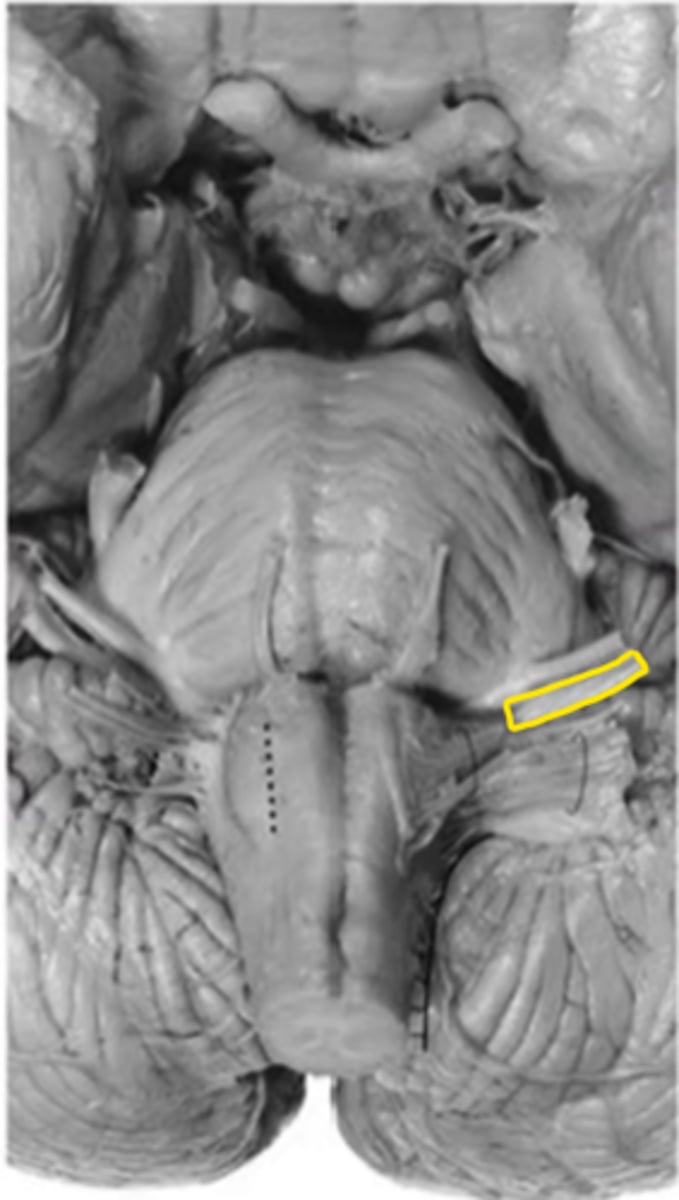

olive

ID the structure

pre-olivary sulcus